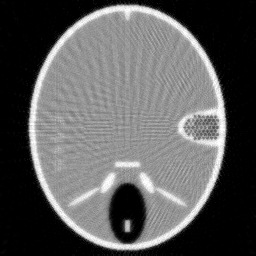

Figure 2. Results of different methods for reconstructing the head phantom with underdetermined rate 25% and relative noise level 0.2. (a) FBP (SNR=0.3253), (b) Landweber (SNR=0.1718), (c) Kaczmarz (SNR=0.1406), (d) L2-TV with scalar λ𝜆\lambda (SNR=0.0644), (e) Our method (SNR=0.0525), (f) λ𝜆\lambda in our method.

Example 1. Our first test example is on the simulated head phantom, which is generated in a square domain of 256×256256256256\times 256 pixels, i.e., there are 2562=65,536superscript256265536256^{2}=65,536 unknowns. With 362 beams and 45 projection angles, the correspond CT reconstruction problem has an under-determined rate of 25%. The measurements are given by f=Au¯+ϵ𝑓𝐴¯𝑢italic-ϵf=A\bar{u}+\epsilon, where u¯¯𝑢\bar{u} is the ground truth (the true attenuation coefficients in the object) and ϵitalic-ϵ\epsilon denotes the additive white Gaussian noise with the noise level ϵ/Au¯normitalic-ϵnorm𝐴¯𝑢\|\epsilon\|/\|A\bar{u}\|.

In order to study the behaviour of our method, we compare it with the filtered back-projection (FBP) algorithm [15], the Landweber method [15], the Kaczmarz’s method [8], and the L2-TV reconstruction method, which solves the variational model (1) with TV regularization as proposed in [19]. All methods are solved under a non-negativity constraint. Note that in the L2-TV method the regularization parameter α𝛼\alpha is scalar, which is chosen to give the largest signal-to-noise ratio (SNR).

In Figure 2 and 3, we give the reconstruction results, which are shown in the same intensity range as the original phantom, from the simulated measurements with the noise level 0.2 and 0.8, respectively. Since the FBP algorithm is according to the analytical formulation of the inverse X-ray transform, it implicitly requires to have continuously measured clean data from the whole 0 to π𝜋\pi angular range. Therefore, it is not suited for reconstructing from noisy limited data. We can clearly see many stripe artifacts due to the noise and sparse projection angles in the FBP results. Both the Landweber and Kaczmarz’s methods perform better than FBP, but there are still some visible artifacts in the reconstruction. By using the TV regularization in the L2-TV and our methods, we potentially assume that the reconstructions are piecewise constant, which evidently reduces the influence of the noise and avoids stripe artifacts. In addition, comparing the results from the L2-TV and our methods, we find that our method suppresses artifacts much better while reconstructing most details. For instance, the grey region in the head and the black dotted region on the right side. With respect to SNR, it is also clear that our method gives the best reconstruction results. In Figure 2 (f) and Figure 3(f), we also plot the λ𝜆\lambda function obtained by our method. One can see that in the more textured regions λ𝜆\lambda is large in order to preserve the details, and in the more homogenous regions it is small to reduce artifacts.